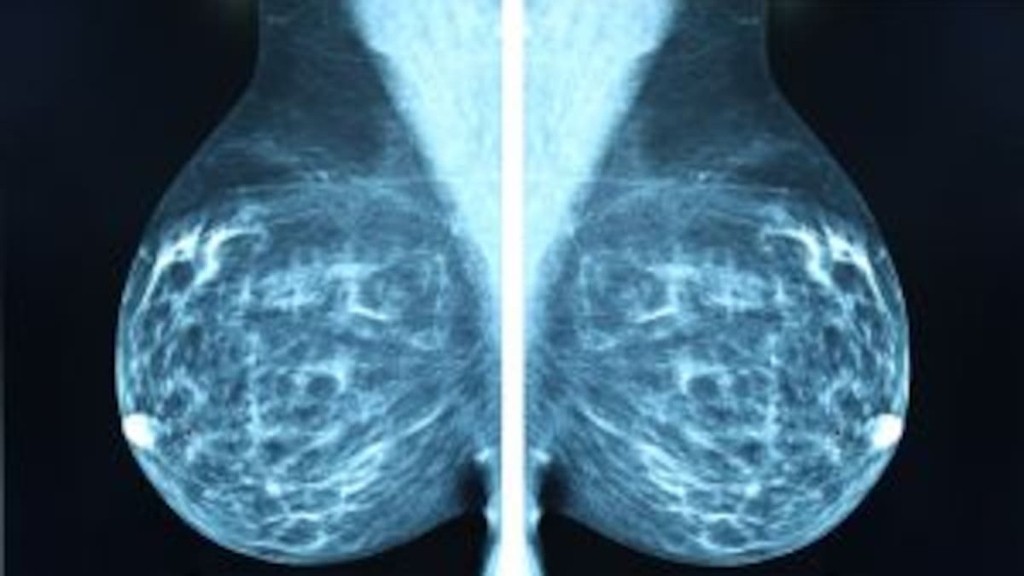

Se dio una orden para dejar de informar a las mujeres sobre sus mamografías, responsabilizando al hospital, con cambios en sistemas informáticos y subcontrataciones.